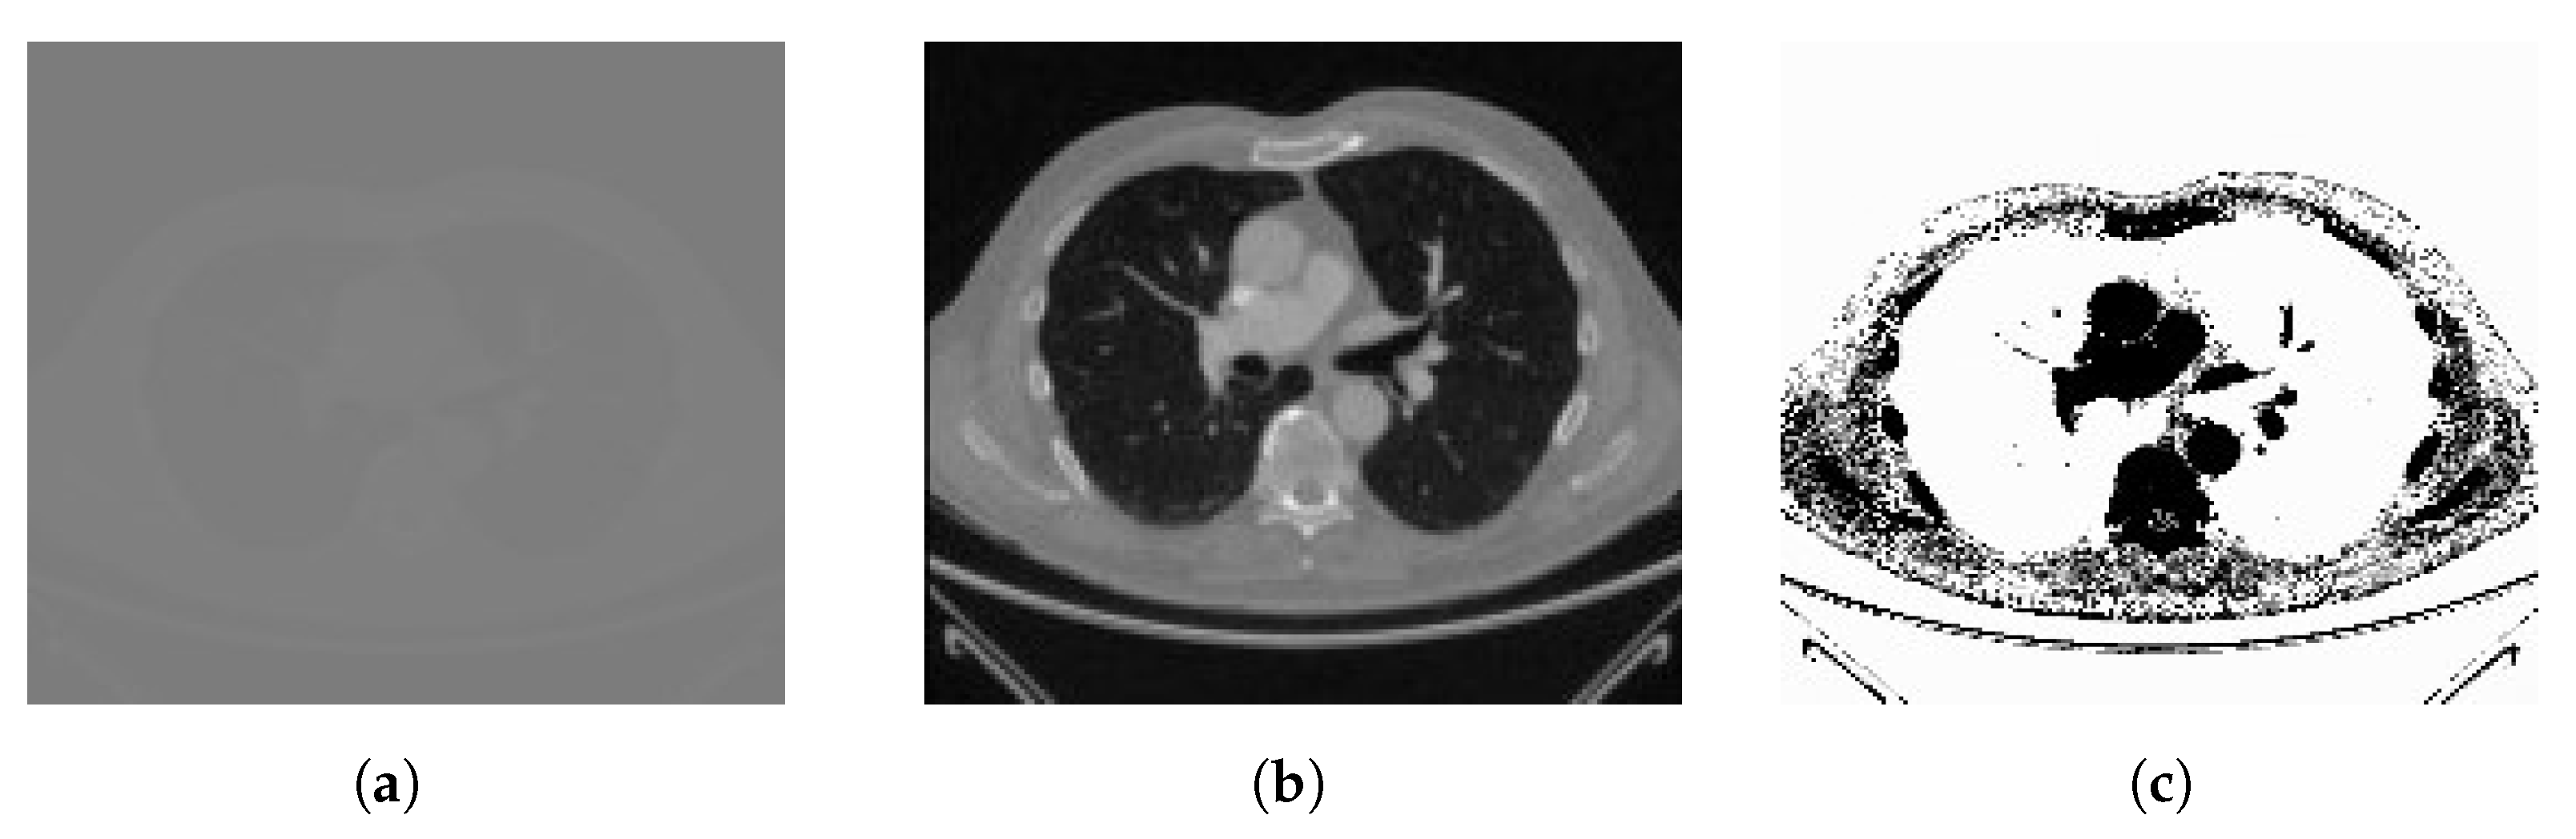

3.1.1. Lung CT Scan Dataset [81]

3.1.3. Ground-Truth Annotations

3.2. Dataset Preprocessing

3.2.1. Image Conversion to 8-bit

3.2.2. Grayscaling

3.2.3. Image Enhancement with Histogram Equalization (HE)

3.2.4. Image Adjustment